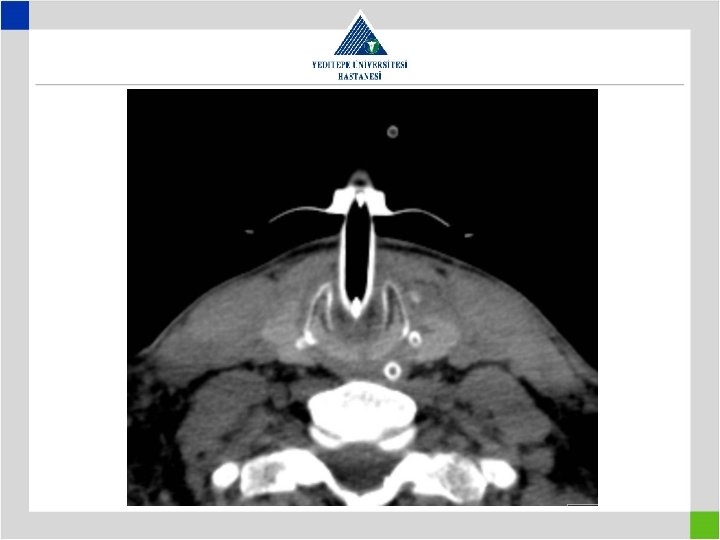

Diagnosis • Stenotic segment calculation to be correct • CT image in supine position may falsly indicate a preglottic stenosis – Overresection – increased anastomotic tension – restenosis • Pediatric trachea tolerates the tension poorly in comparison with adults – Insufficient resection – remaining fibrosis – restenosis

Iatrogenic Factors • Metal stents in bening tracheal conditions cause elongation of pathologic segment and cause the patient to loose the previously present chance of surgical cure